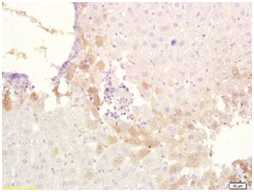

Tissue/cell: rat liver   tissue; 4% Paraformaldehyde-fixed and paraffin-embedded;

Antigen retrieval: citrate   buffer ( 0.01M, pH 6.0 ), Boiling bathing for 15min; Block endogenous   peroxidase by 3% Hydrogen peroxide for 30min; Blocking buffer (normal goat   serum) at 37 for 20 min;

Incubation: Anti-ABCB6   Polyclonal Antibody, Unconjugated 1:200, overnight at 4°C, followed by   conjugation to the secondary antibody and DAB  staining